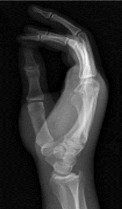

- الأشعة السينية (X-rays): هي الخطوة الأولى في تقييم الكسور، الخلوع، وتغيرات التهاب المفاصل. تساعد في تحديد مدى تدهور العظام والمسافات المفصلية. على سبيل المثال، تُظهر صور الأشعة السينية كسور السلاميات

أو كسور قاعدة العظم المشطي الخامس